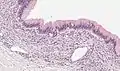

| Micrograph showing a mucinous cystadenoma of the ovary. H&E stain. | |

Mucinous cystadenoma is a benign cystic tumor lined by a mucinous epithelium. It is a type of cystic adenoma (cystadenoma).

Mucinous cystadenomas make up 15–20% of all ovarian tumors. They often become very large and can extend up into the abdomen.

Benign mucinous cystadenomas compose 80% of mucinous ovarian tumors[2] and 20–25% of benign ovarian tumors overall. The peak incidence occurs between 30 and 50 years of age. Benign tumors are bilateral in 5–10% of cases.